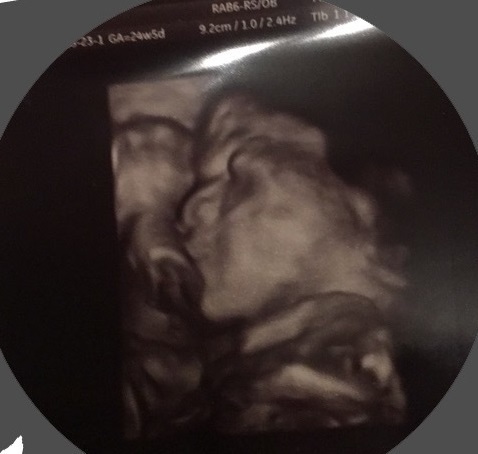

みんなの妊娠24週目のエコー写真をご紹介します。

24週0日(24w0d・女の子)|ゆっちゃんちゃん さん(32歳)

エコー写真撮影時のエピソード:

前回の健診では、顔を手で隠していて見せてくれなかったけれど、この健診では顔をはっきり見せてくれてうれしかったです。

またこの次の健診では顔を隠していました。 なかなかはっきり見せてくれるときが少ないです。